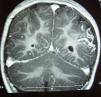

La TC craneal mostró una calcificación curvilínea con impronta en la calota craneal (Figura 1). La RM y angio-RM cerebral mostraron en área cortical parieto-occipital izquierda pequeñas áreas de hiposeñal, con leve hipotrofia y sin dilatación de arterias de mediano y gran tamaño.

Figura 1. TC sin contraste: corte axial; se aprecia imagen hiperdensa con aspecto curvilíneo en región parieto-occipital izquierda con leve impronta sobre la calota craneal.